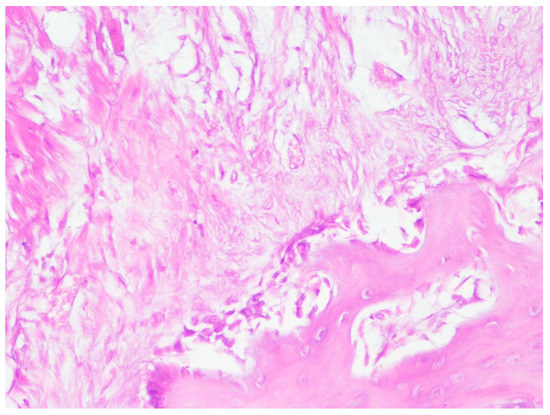

Histological examination of osseous tissue around the orthopedic screws demonstrated no evidence of granulomatous inflammation. In the area close to the implant there was a layer of dense fibrotic tissue with fibroblasts and fibrotic tissue with a trabecular structure and non-mature osseous tissue with loop-like structures (Figure 7).

A definitive layer of osseous tissue, with many visible osteoblasts on the periphery, surrounded the implant edge. The osteoblasts had a typical cylindric form with some large dark nuclei. No endochondral ossification was noted. Multiple osteoblasts were seen close to the new bone trabeculae. There was reticular tissue growing between the trabecular space with evidence of neoangiogenesis (Figure 8).

Figure 7. Reactive osteogenesis near the titanium implant.

Figure 8. Fibrosis and maturing bone near the titanium implant.